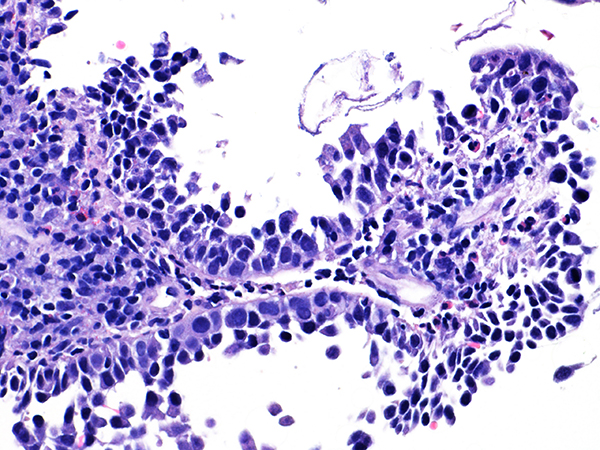

Soft Bx CIN 2 10x - Low Power

Area 1 - Soft Bx CIN 2 40x - High Power |